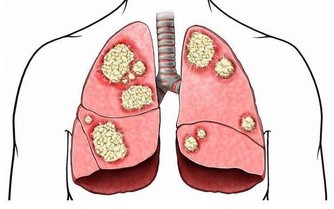

癌症先兆是可以警示我們應該及早預防癌症,但是我們往往會忽視這些疾病徵兆,以至於「病來如山倒」。

今天小編想要和大家分享的是胃癌的一些常見徵兆。

那麼,胃癌到底有哪些徵兆呢?胃癌如何預防最有效呢?一起來看一下!